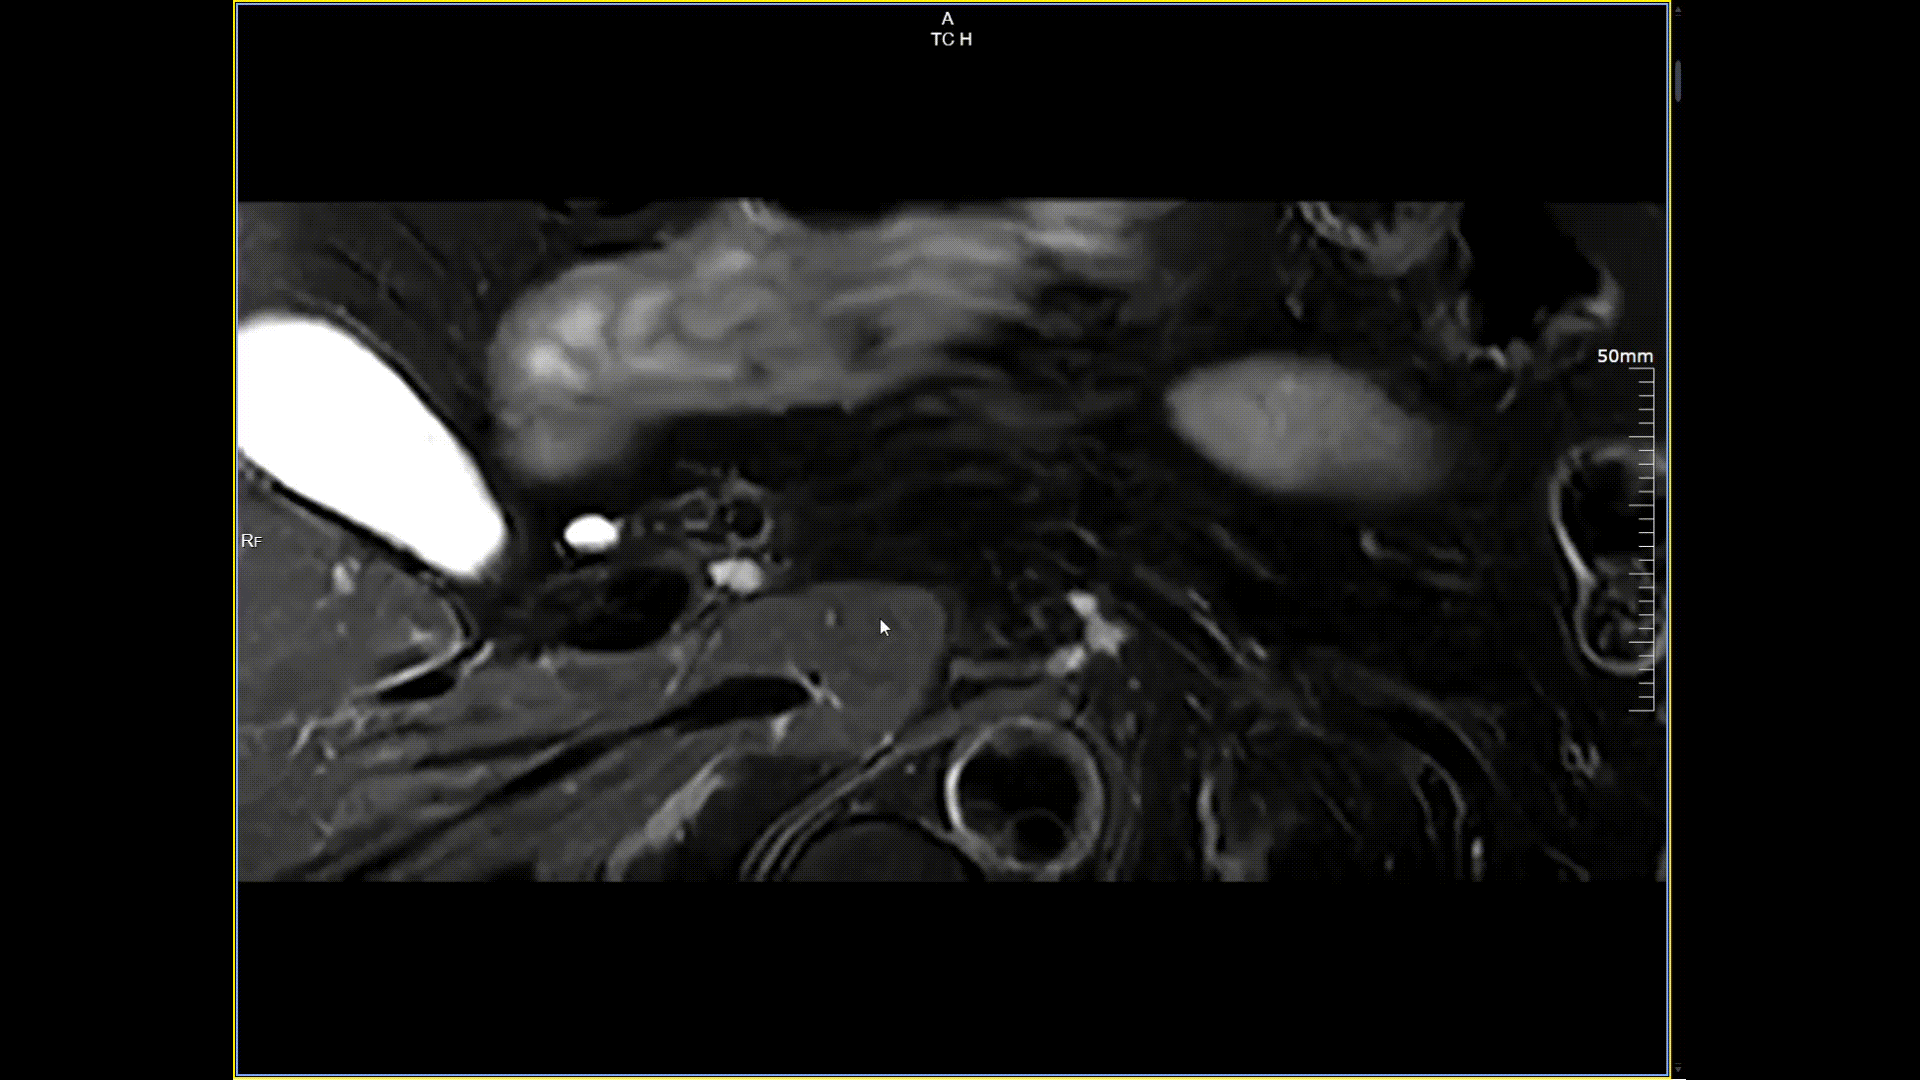

胰腺小视野高分辨,分辨率0.5*0.5mm

5.0T磁场强度远高于其他设备,使得氢原子核在磁场中的响应信号极大地增强。这就像在安静的房间里能听清细微的声音一样,高信噪比能让医生看到更微小、更模糊的病变结构。例如上述患者的检查,该设备可以呈现0.2x0.2毫米高分辨率的图像以及动态显示血管走行,使得病变血管的细微解剖结构、分布及其与周边脑组织的关系得以直观呈现,为临床医生进行精准诊断并制定后续治疗方案提供了重要的影像学依据。